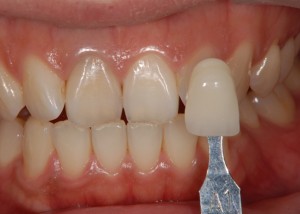

ホワイトニングをスタートする前に、まず色見本で、現在の歯の色を確認します。

(当院では実際に、このように写真を撮って記録を残すようにしてます)

神経の取ってある歯は、だいたいA3という色でした。

そのお隣の歯は、A1という色。

もともと、かなり白目のかたですね。